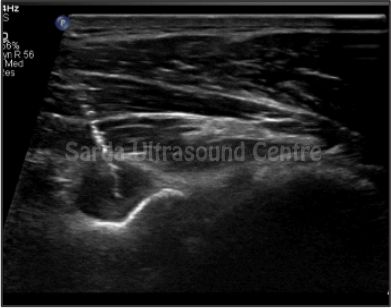

Our facility offers comprehensive range of ultrasound-guided interventions such as FNAC, biopsies, injections and aspirations, ensuring precise and safe treatment for our patients.

With Detailed pre-procedure councelling, High resolution ultrasound machines, Significant experience in using ultrasound for guided procedures, maintainance of sterile environment ensuring highest level of safety; we are committed to providing the highest standard of care for all ultrasound guided interventions.